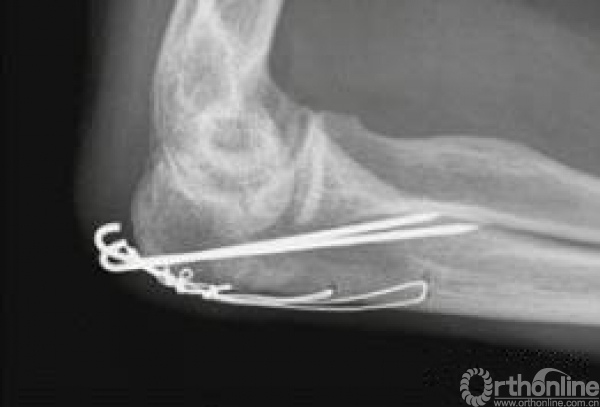

张力带的技术点也得说一下(简单骨折):

1.纵劈肱三头肌;

2.将克氏针放到肌腱下,克氏针的长度要长可到80-90;

3.八字固定在肘关节伸直位远端大约4-5cm处;

4.可用克氏针也能用空心钉;

5.一定要解剖复位的时候拧入,否则容易错位。